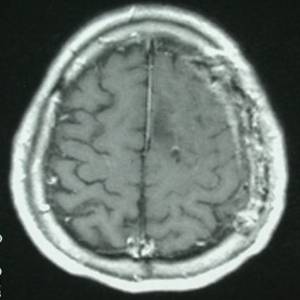

行显微手术切除肿瘤,simpsonII级全切除。术后照片如下,术后病人偏瘫缓解。

术后照片